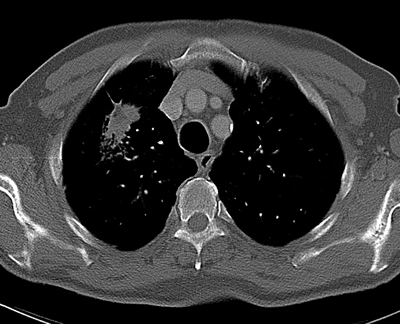

Cáncer de pulmón